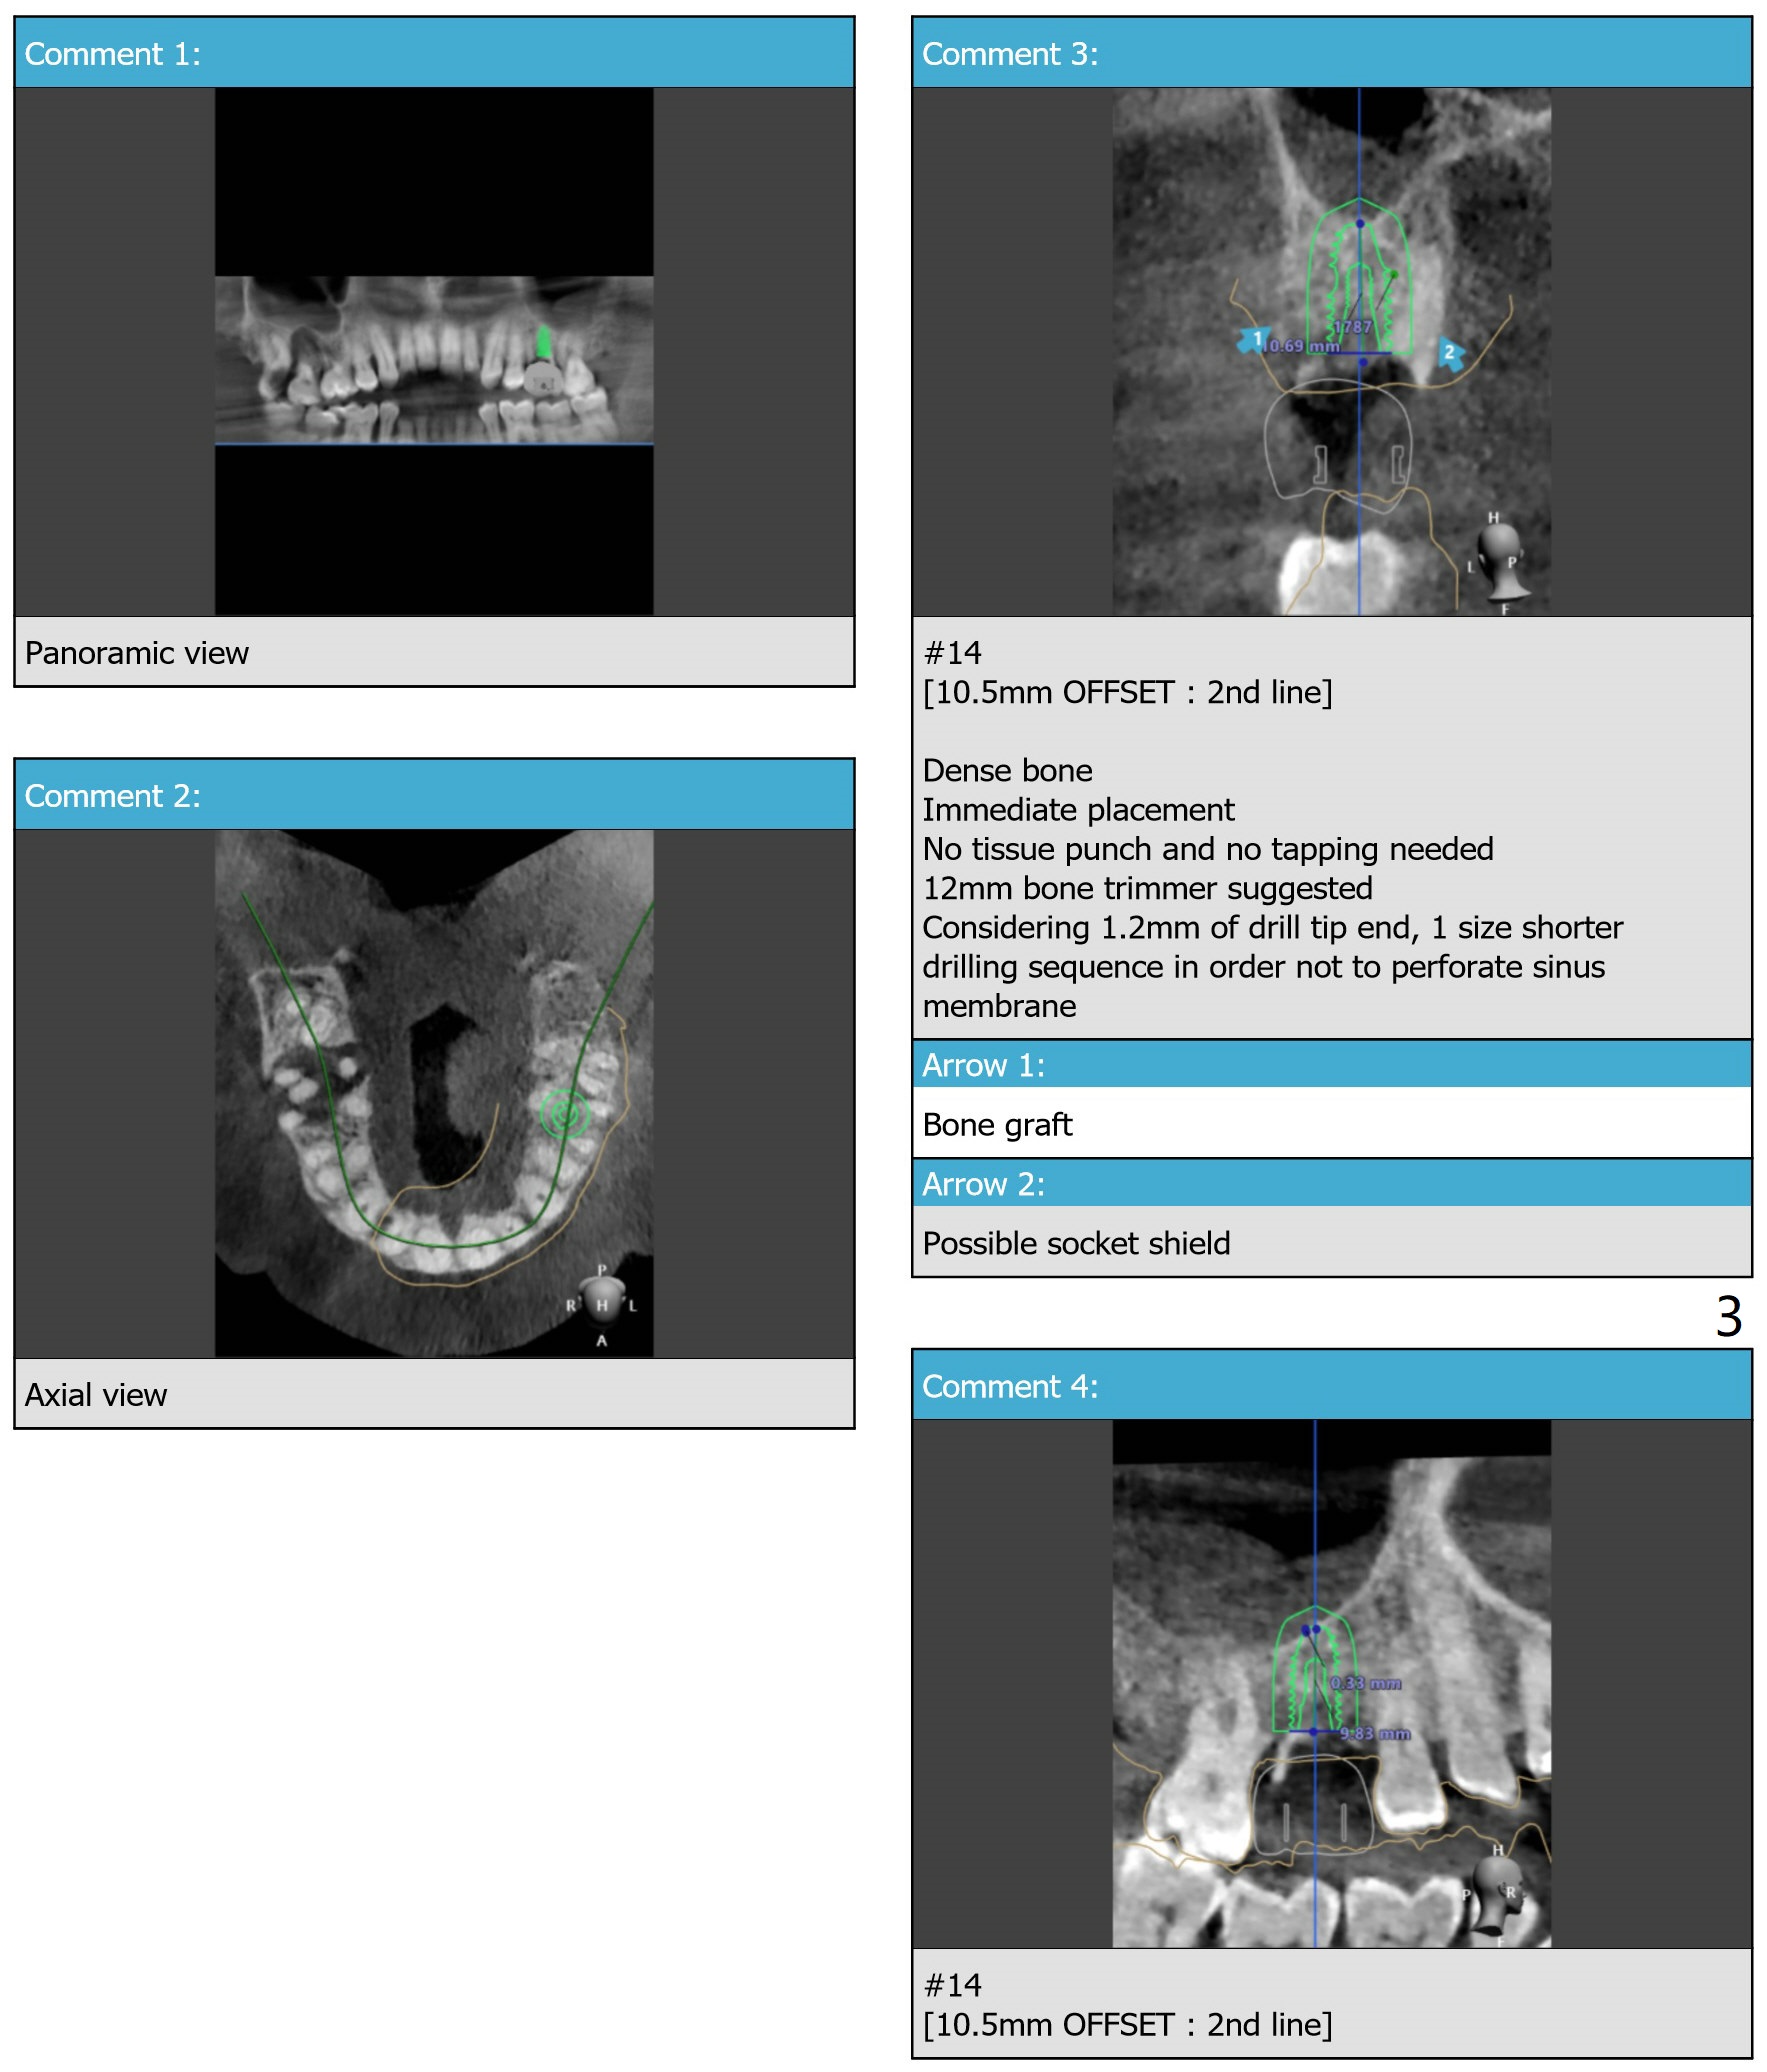

Upper Molar Immediate Implant Shield Trajectory II Shield Xin Wei, DDS, PhD, MS 1st edition 10/30/2019, last revision 02/21/2021